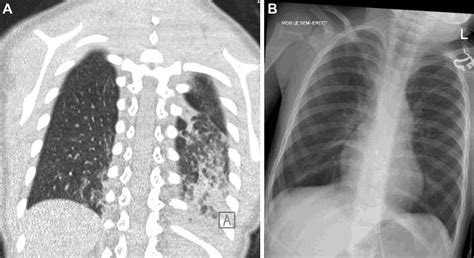

Once the scan is completed, a radiologist will interpret the images and generate a report. When viewing a Pneumonia CT Scan, medical professionals look for specific patterns of lung involvement. These patterns often indicate the type of pneumonia or the severity of the inflammatory response.

Common findings often described in reports include:

• Consolidation: This refers to the filling of air spaces (alveoli) with fluid, pus, or other material, appearing as dense, white areas on the scan.

• Ground-Glass Opacity (GGO): A hazy appearance in the lungs, indicating partial filling of air spaces or thickening of the lung interstitium. This is often seen in viral pneumonias.

• Pleural Effusion: The buildup of fluid in the space between the lung and the chest wall.

It is important to remember that these findings must always be correlated with the patient's symptoms, laboratory results, and clinical history. A report with "positive findings" does not always imply a worst-case scenario, as many patterns are typical of common bacterial or viral infections.